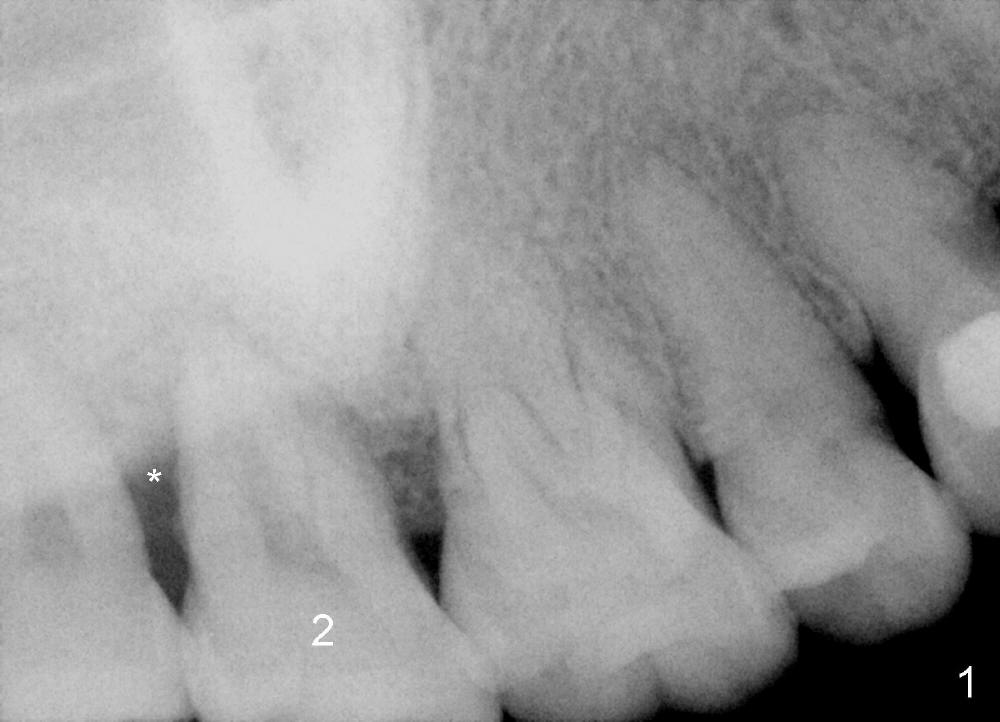

A 48-year-old lady is a dental phobic and has generalized chronic periodontitis. Bone loss around the tooth #2 has been severe for the last 5 years (Fig.1,2 *). Finally she agrees to have #2 (symptomatic) extracted and immediate implant placed (Fig.3 I). A 7x17 mm implant has to be used to achieve primary stability. The remaining buccal and lingual gaps are filled with allograft and membrane (Fig.4 *). Fig.5 shows that there is a space between the tooth #1 (asymptomatic) and the immediate implant (I). The wound/socket is protected by applying perio dressing around an abutment (Fig.6 A). Postop the patient is pain free; the perio dressing dislodges by itself. She returns 3.5 months later for restoration; but the tooth #1 has shifted mesially (Fig.6 arrow). The patient is not so willing to have #1 removed. Bands and bracket are placed in the neighboring teeth including a provisional crown to move the shifted tooth (with mobility) distally (Fig.7,9). The 2nd reason for #1 shifting is abnormal occlsual scheme on the right posterior region (Fig.8); mobility of #1 is the 1st one. The 3rd one is probably bruxism. In 5-6 weeks, the tooth #1 has moved to a desirable position (Fig.10, as compared to Fig.3,5). There is enough space for restoration (Fig.11,12).